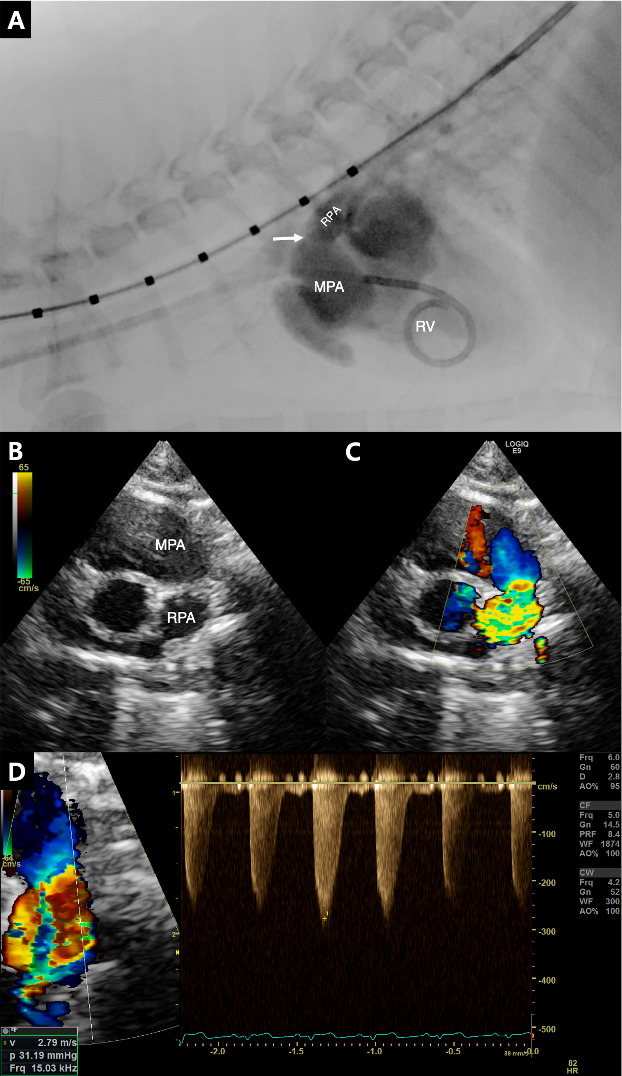

一只4个月大的英国短毛小猫被转到我们的研究所进行心脏杂音的评估。胸片和超声心动图显示右肺动脉狭窄,伴右心房扩张和右心室肥厚。通过狭窄病变的收缩血流速度为6.15 m/sec,压力梯度为151.42 mmHg。计算机断层扫描证实右肺缩窄同时伴有左肺动脉中断。行球囊血管成形术,收缩血流速度由6.15 m/sec降至2.79 m/sec,缓解右心室压力过载。一年后,胸片显示左肺萎陷和右肺恶性膨胀;然而,患者仍然无症状。在诊断后33个月,患者继续茁壮成长,没有任何临床症状。

A 4-month-old, British Shorthair kitten was referred to our institute for evaluation of a heart murmur. Thoracic radiography and echocardiography revealed narrowing of the right pulmonary artery, accompanied by right atrial dilation and right ventricular hypertrophy. The systolic flow velocity across the stenotic lesion was 6.15 m/sec, with a pressure gradient of 151.42 mmHg. Computed tomography confirmed right pulmonary coarctation with concurrent interruption of the left pulmonary artery. Balloon angioplasty was performed, reducing the systolic flow velocity from 6.15 m/sec to 2.79 m/sec and relieving right ventricular pressure overload. One year later, thoracic radiography revealed left lung collapse and right lung hyperinflation; however, the patient remained asymptomatic. At 33 months post-diagnosis, the patient continued to thrive without any clinical signs.